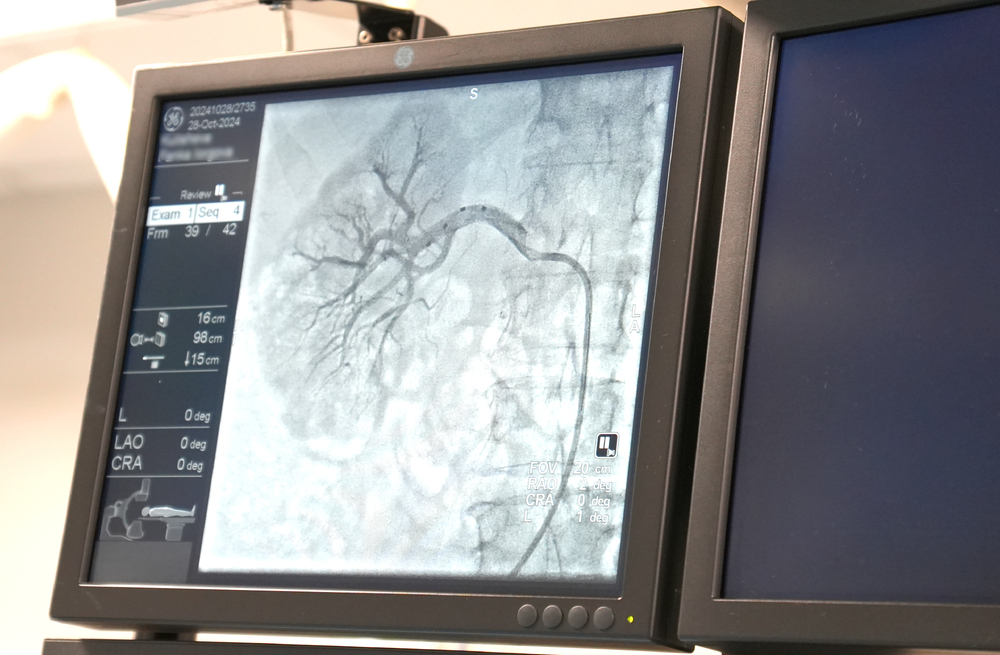

Снимка: Лечебни заведения "Медика"

Реналната денервация е нов и обещаващ минимално инвазивен метод, основан на връзката между бъбреците и кръвното налягане. При процедурата чрез специален катетър се достига до бъбречната артерия, където се провежда радиофреквентна аблация на нервните окончания, което намалява тяхната активност и съответно артериалното налягане. Едноваскуларната процедура се осъществява в ангиозала с локална упойка.

Първите двама пациенти, на които е приложен методът в „Медика“, са 66-годишна жена и мъж на 70 години с коронарна болест и трети стадий хипертония. Още на следващия ден кръвното им спада съществено и те се чувстват по-добре.

За положителния резултат от процедурата говорят показателите на пациентите. Преди нея жената, въпреки лекарствената терапия, е поддържала кръвно налягане от порядъка на 240 – 260/140 mm Hg, а след процедурата то вече е 110/80. Мъжът при постъпване в болницата е бил с горна граница е 180, а след реналната денервация кръвното му е нормализирано.